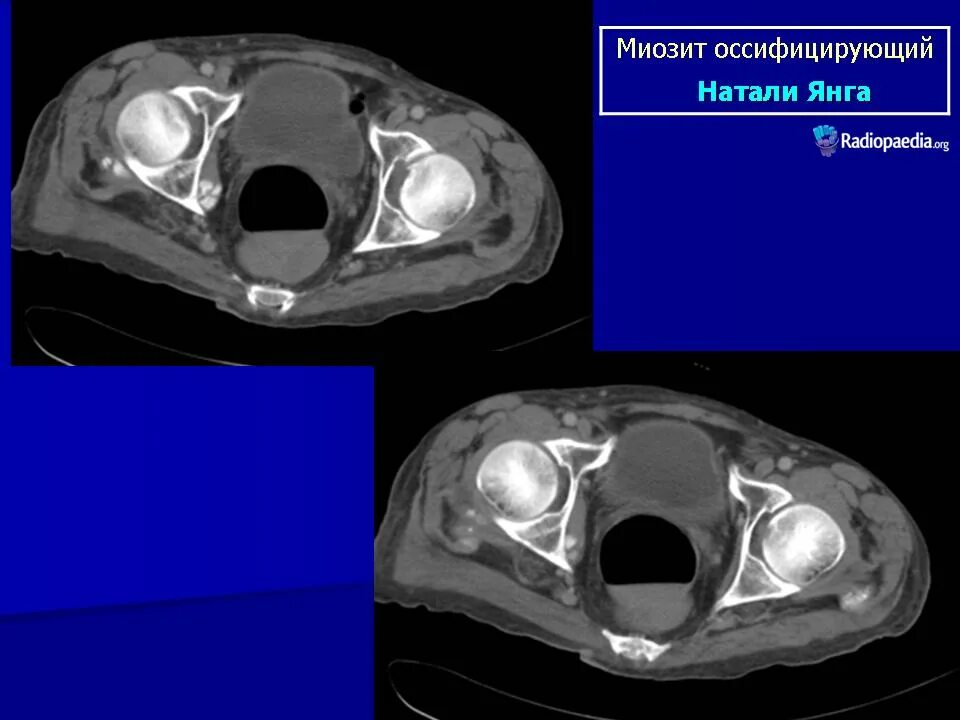

Оссифицированный миозит